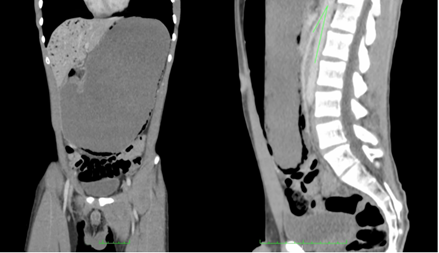

A su ingreso a urgencias iniciaron hidratación con líquidos endovenosos y manejo antiemético. Fue valorado por Cirugía general y se decidió realizar una TC, en la que documentaron una marcada dilatación del estómago, el cual casi contactaba el domo de la vejiga, con neumatosis de la pared, predominantemente en el borde inferior y la curvatura mayor del estómago, asociado a aire en la vena porta, el cual se pudo diferenciar de la neumobilia, dado que comprometía los 2 cm más cercanos a la cápsula de Gleason. En la revisión detallada de la imagen, se documentó un ángulo áorto-mesentérico de 16 grados en el corte sagital y una distancia entre la aorta y la AMS de 2,5 mm en el corte axial (Figura 1). Se confirmó el diagnóstico de síndrome de pinza mesentérica.